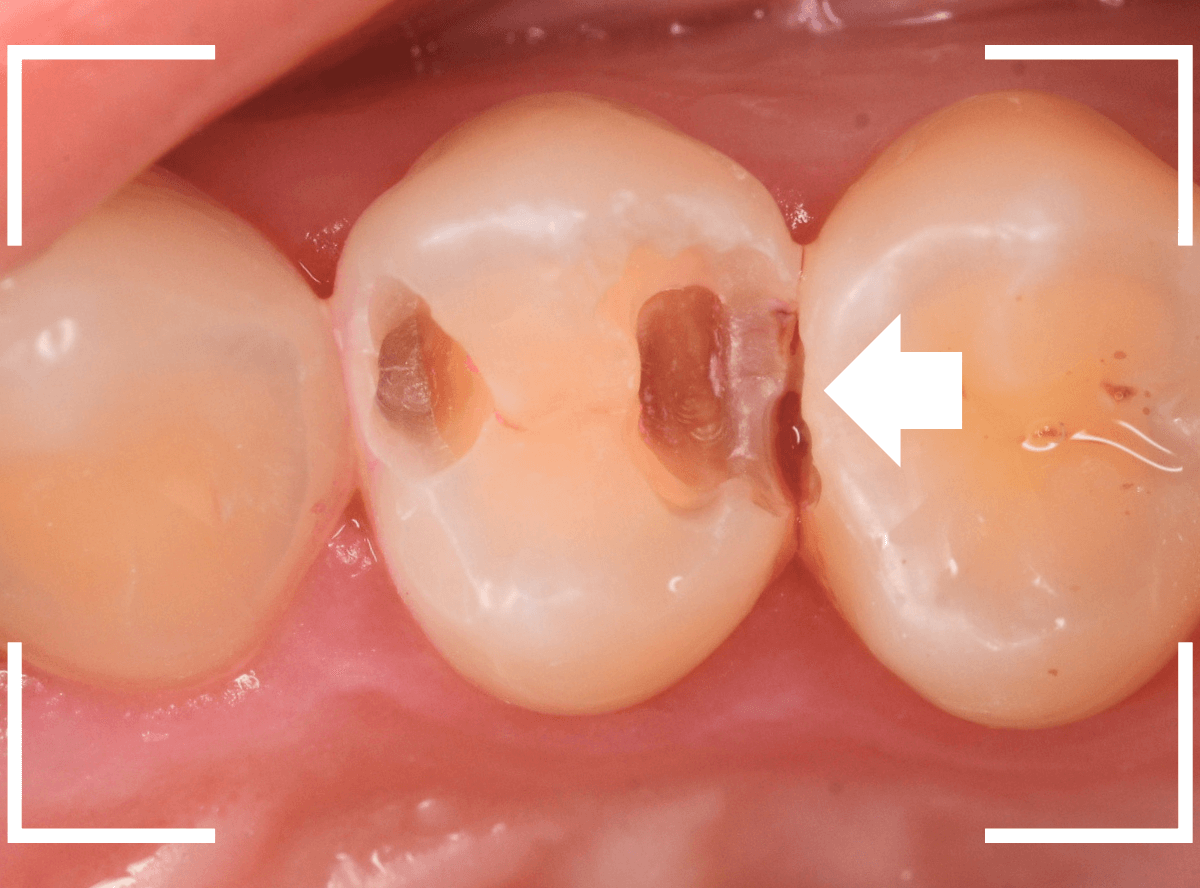

Case.13 歯と歯の間の虫歯が4本続いたケース

他の歯の虫歯の治療で来院された方で、下の歯の奥歯に虫歯が見つかった方です。

レントゲン写真で、歯と歯の間が虫歯になっているのがわかります。

手前の歯の状況です。

〇部のやっと黒く見えている部分が虫歯です。

後ろの歯の状況です。

〇部に虫歯がある他に、矢印部、歯と歯の間に物がつまっているのが見えます。

このような状況の時は、中で大きな虫歯になっている事が多いです。